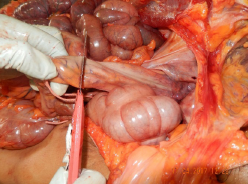

El presente caso clínico se abordó mediante la aplicación de la Exenteración Pélvica Total (EPT), un procedimiento de "vaciamiento pélvico o apertura pélvica" que permite una exploración exhaustiva de la región pélvica. La técnica quirúrgica se ejecutó meticulosamente siguiendo los siguientes pasos:

Se divulsiona tejido cutáneo, tejido celular subcutáneo y tejido muscular mediante incisión que bordea implantación de vello púbico que sigue región inguinal derecha e izquierda bordeando región perianal hasta bordear región anal, desprendiendo por planos el tejido blando de la cara inferior de la cavidad pélvica, se individualiza órganos intrapelvicos, se procede a ligar recto a 20 centímetros del esfínter anal externo y se procede al retiro en bloque de periné, genitales externos e internos, órganos intrapelvicos, genitales internos, observándose:

Tras la detallada aplicación de la exenteración pélvica total, el examen interno de las estructuras pélvicas reveló la presencia de diversas lesiones consistentes con violencia sexual severa. Los hallazgos principales en el canal vaginal y su periferia se resumen en la Tabla 1, mientras que las lesiones identificadas en la región anal se detallan en el la Tabla 2. Adicionalmente, se documentaron visualmente las siguientes lesiones, ilustradas en las figuras 15 y 16, que acompañan este caso.